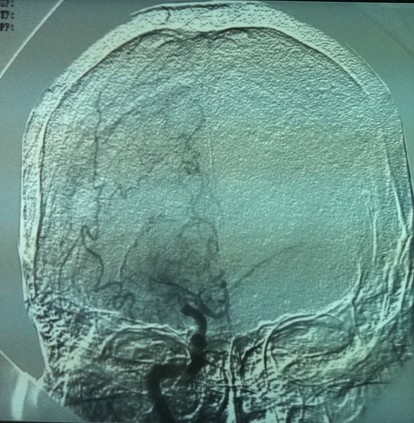

造影见右侧颈内动脉成残端

在微导丝引导下通过微导管进行接触性动脉溶栓

35mg r-tPa溶栓后见右侧颈内动脉开通,大脑前及大脑中动脉显影良好